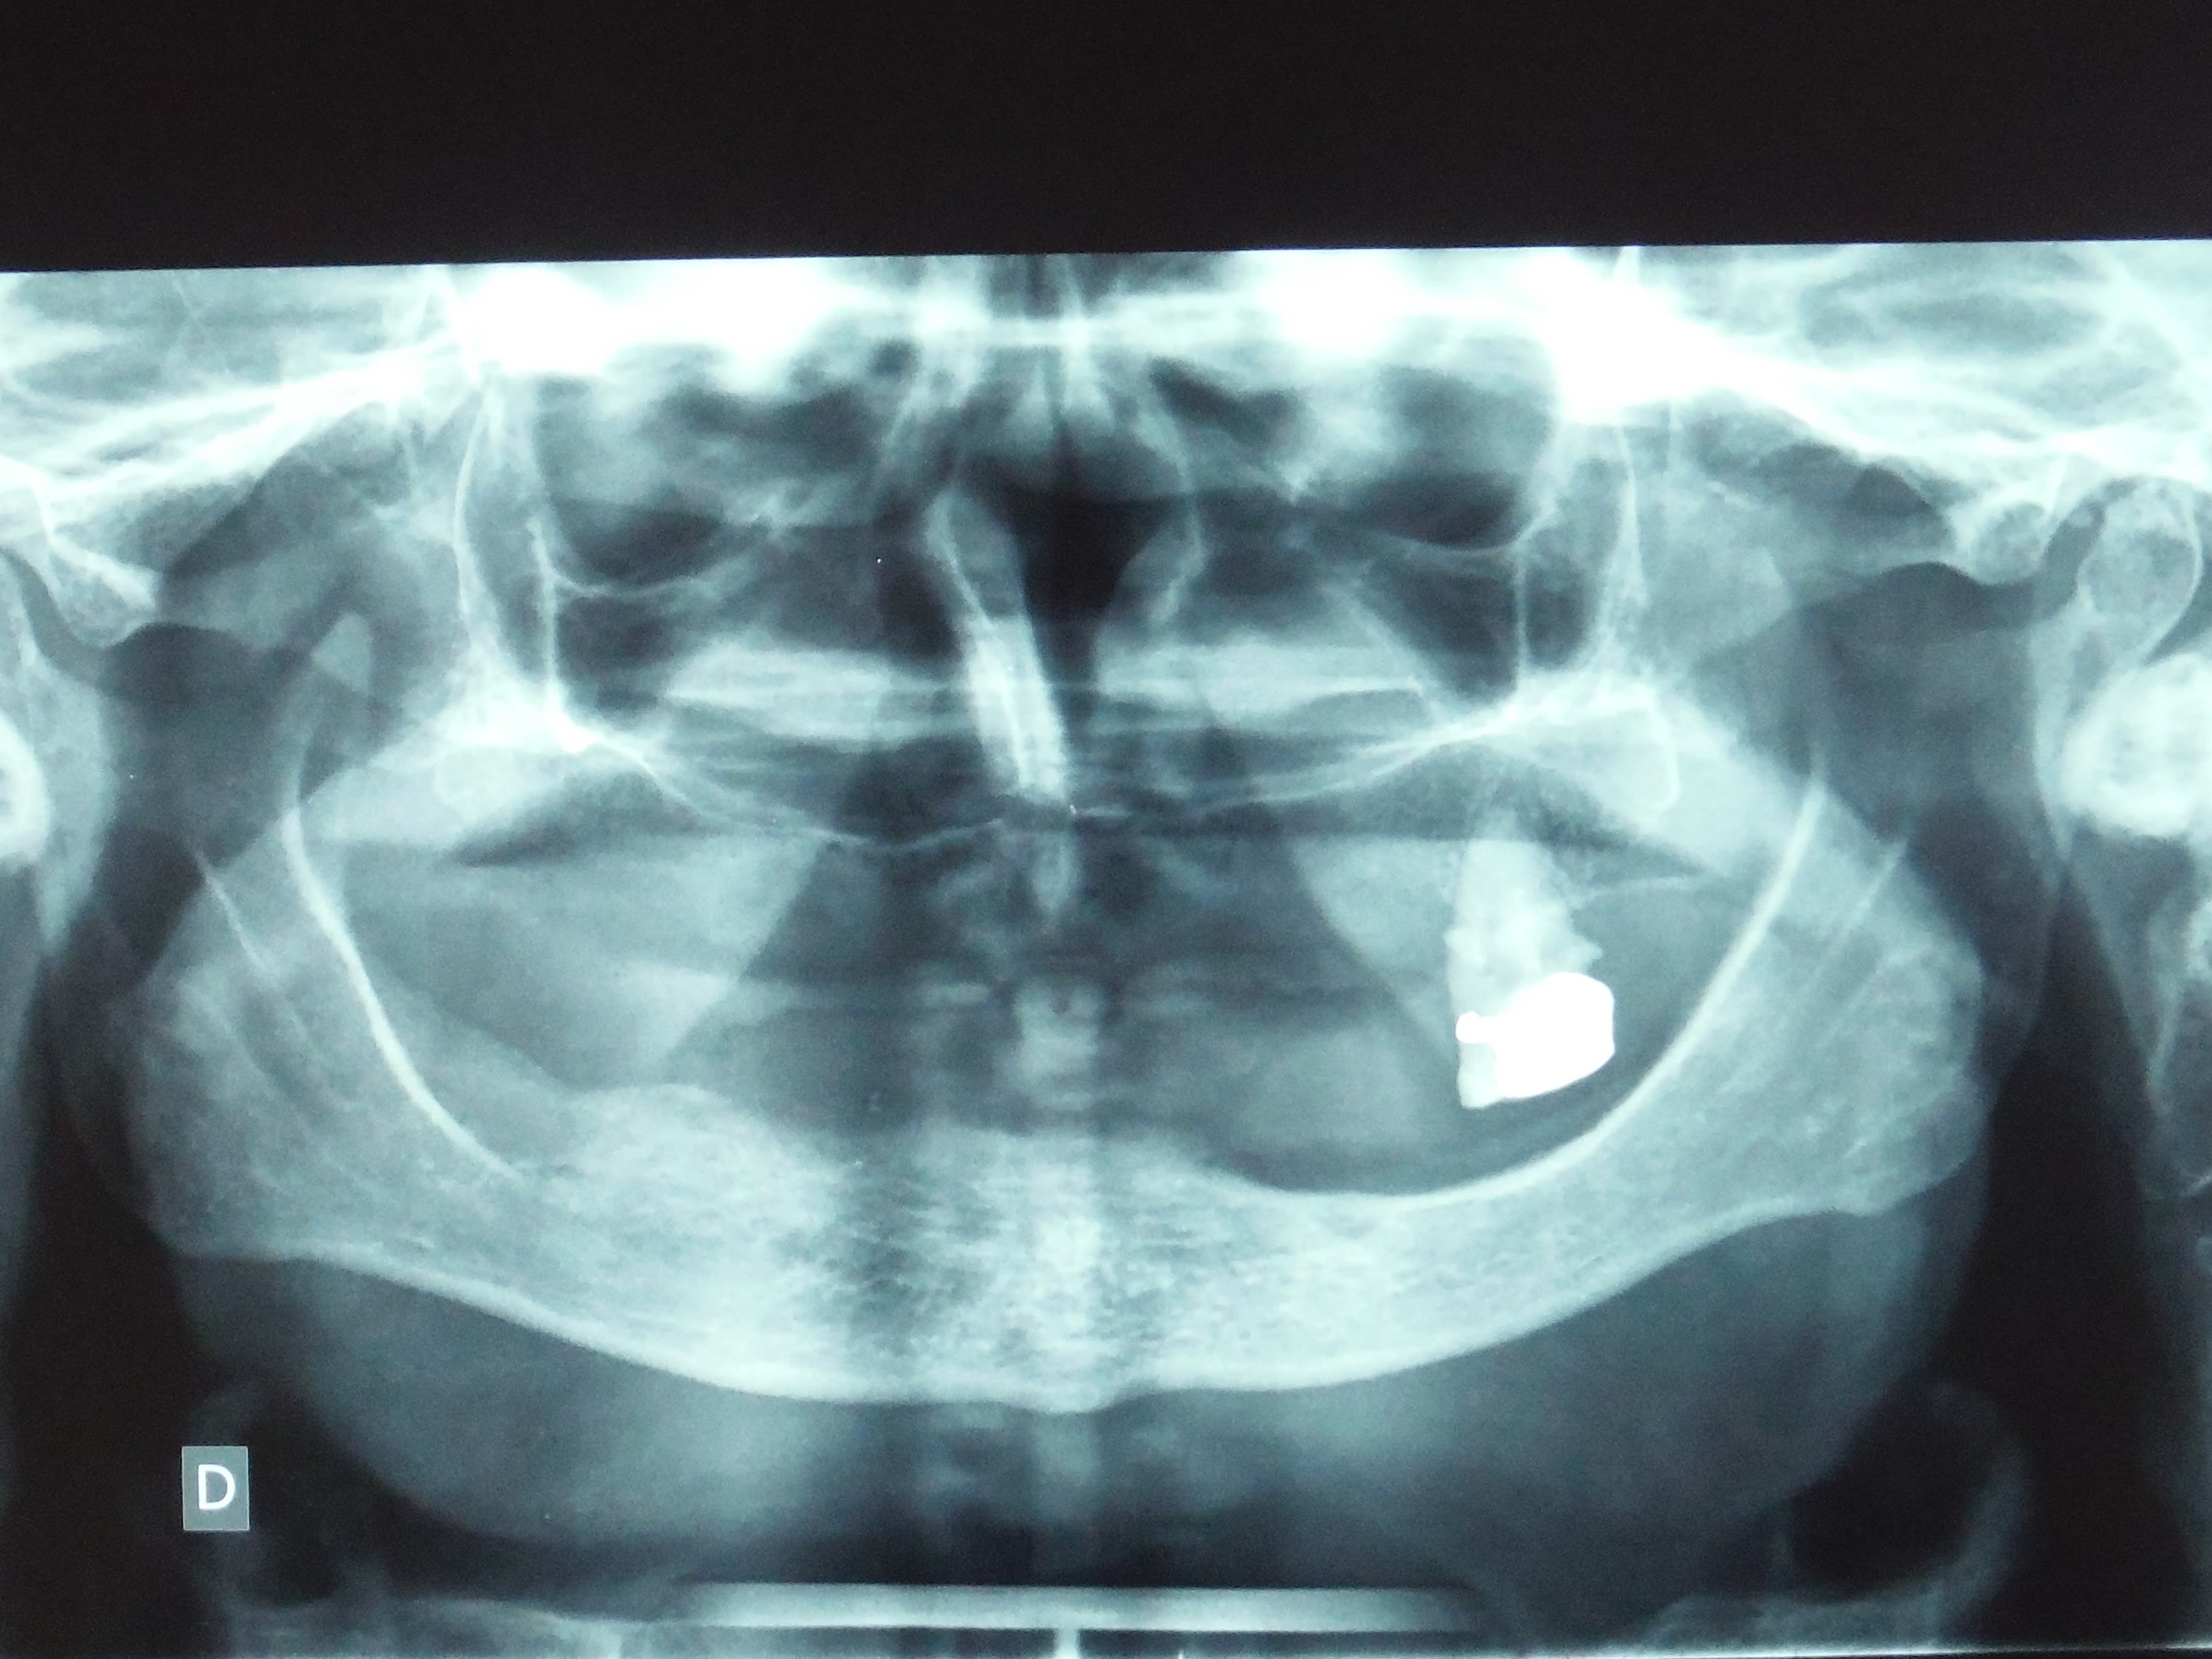

Une crête comme celle-là

la resorption c'est à cause de l'antagoniste :-))

Dscf1629 2 kwcye0 - Eugenol

T'as vu chouette la pano, je suis convaincu que si la molaire maxillaire avait été enlevée, ou bien que les dents prothétiques avaient été en porcelaine, il y aurait eu moins de résorption. c'est pile à l'aplomb de la molaire, je ne crois pas au hasard.